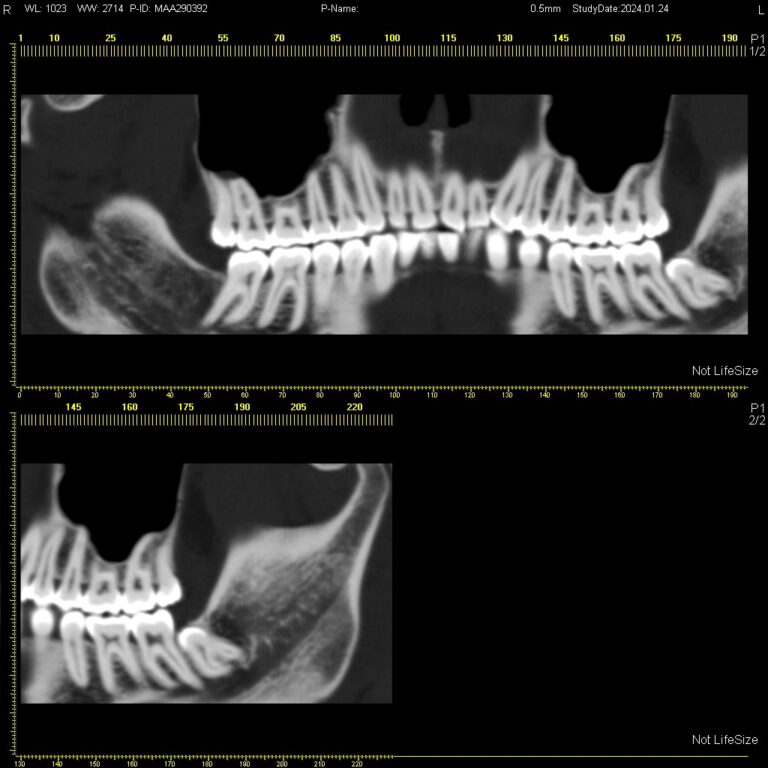

Мультиспиральный томограф выполняет послойное сканирование области верхней и нижней челюстей с помощью рентгеновских лучей, а затем, используя компьютерную обработку данных, создает 3D-модели исследуемой зоны. Современные модели томографов проводят круговое сканирование по спирали, делая срезовые снимки на расстоянии 0,5 мм друг от друга. Затем на основе этих данных реконструируются детальные изображения челюстно-лицевой области в трехмерном формате.

- Информативность. Дентальная КТ позволяет обнаружить признаки патологии, которые не видны на обычных (2D) панорамных снимках – ортопантомограммах. На двухмерных рентгенограммах различные структуры накладываются друг на друга. В отличие от этого пространственные модели дают возможность рассмотреть челюстно-лицевой аппарат в различной проекции и плоскости.

Исследование занимает всего пару минут. Данные, полученные при сканировании, проходят цифровую обработку и выводятся на монитор компьютера в виде 3D-изображений. Врач-рентгенолог внимательно анализирует данные и выдает заключение.

Высокая информативность исследования за счет детальных снимков и наглядных пространственных 3D-реконструкций позволяет увидеть то, что недоступно для визуального осмотра и обычного рентгеновского обследования.